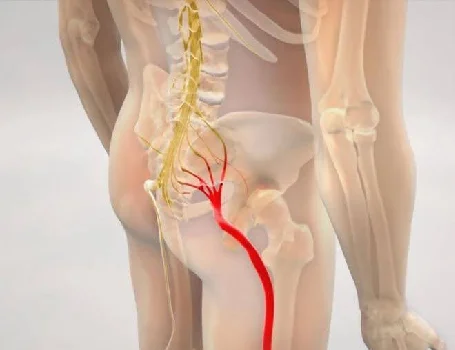

Dolor Ciático: Qué es y Cómo Controlarlo

El dolor ciático es una condición común que afecta al nervio ciático, el más largo y ancho del cuer...